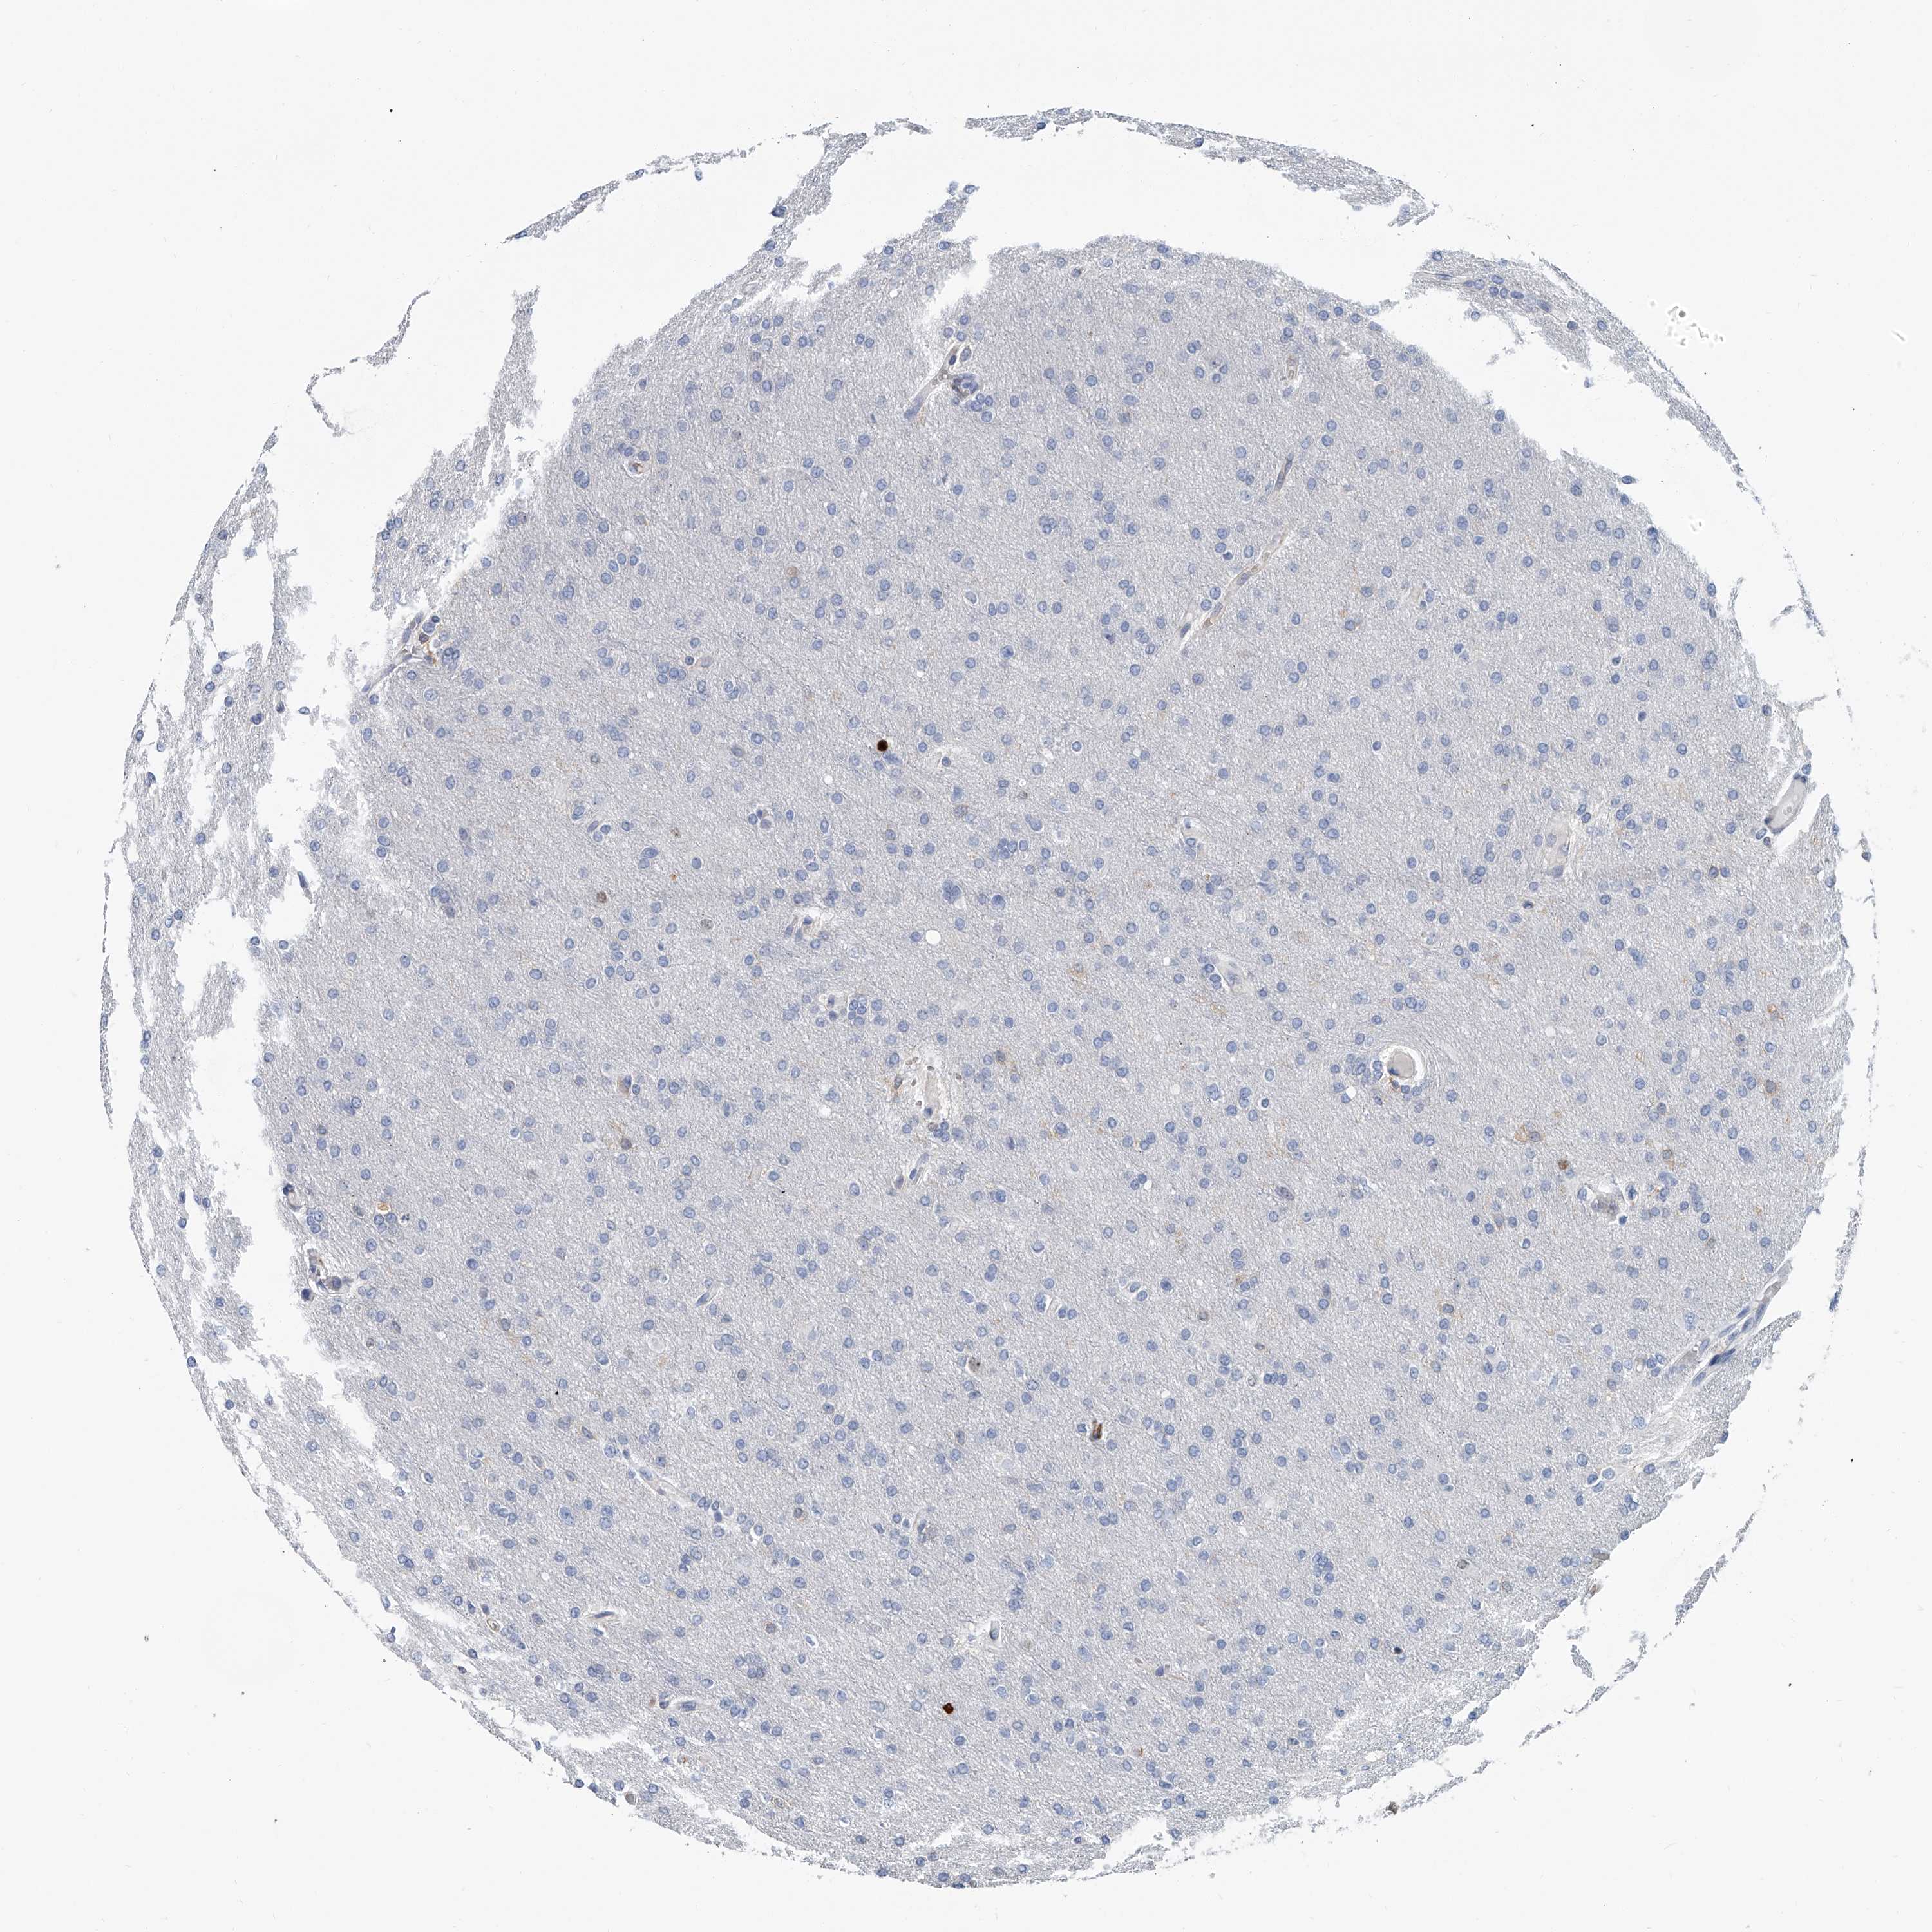

GLIOMA - Protein expressioni

A mouse-over function shows sample information and annotation data. Click on an image to view it in a full screen mode. Samples can be filtered based on level of antibody staining by selecting one or several of the following categories: high, medium, low and not detected. The assay and annotation is described here.

Note that samples used for immunohistochemistry by the Human Protein Atlas do not correspond to samples in the TCGA dataset.

Antibody stainingi

Antibody staining in the annotated cell types in the current human tissue is reported as not detected, low, medium, or high, based on conventional immunohistochemistry profiling in selected tissues. This score is based on the combination of the staining intensity and fraction of stained cells.

Each image is clickable and will lead to virtual microscopy that enables deeper exploration of all samples and also displays staining intensity scores, fraction scores and subcellular localization as well as patient and tissue information for each sample.

Antibody HPA030458

Staining

High

Medium

Low

Not detected

Intensity

Strong

Moderate

Weak

Negative

Quantity

>75%

75%-25%

<25%

None

Location

Nuclear

Cytoplasmic/membranous

Cytoplasmic/membranous,nuclear

Glioma, malignant, High grade

Glioma, malignant, Low grade

Glioblastoma, NOS